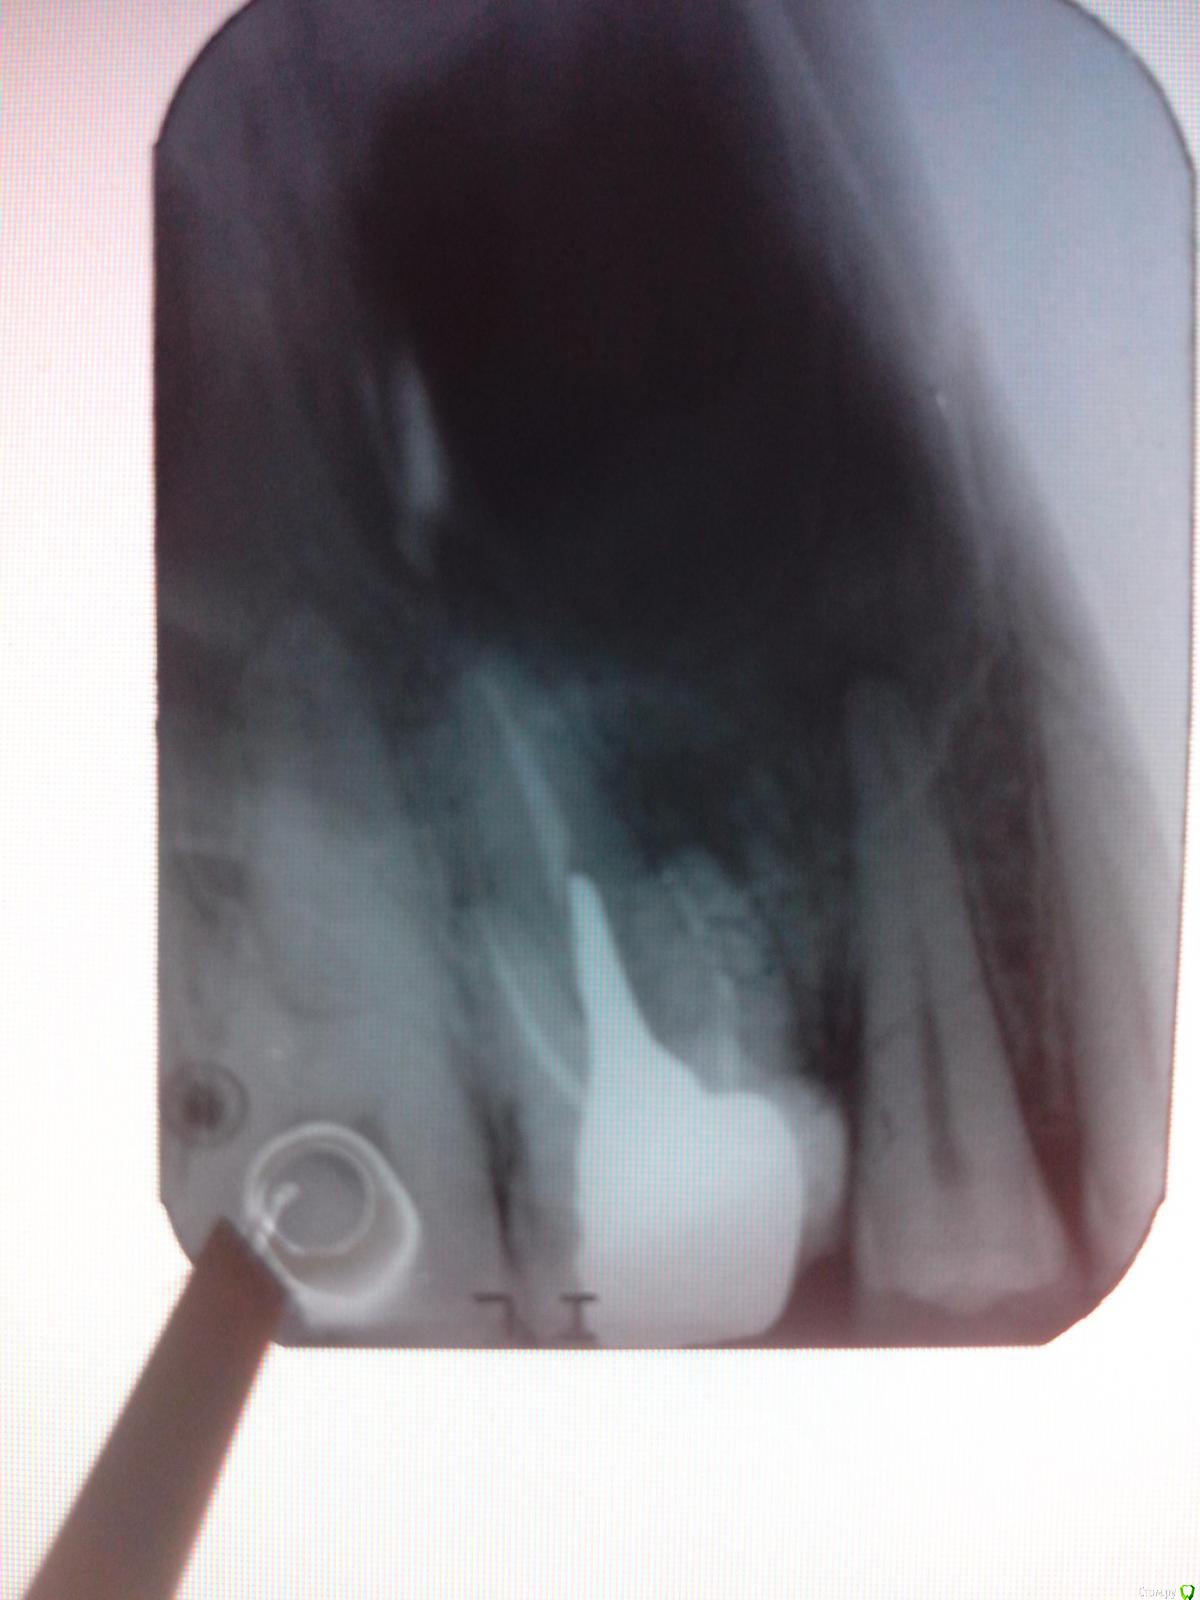

Tellery Опубликовано 17 сентября, 2015 Поделиться Опубликовано 17 сентября, 2015 Три месяца назад отломился кусок от верхней шестерки. Врач сразу стал готовить зуб под коронку. Надрезал, отодвигал ниткой десну, два раза ставил временные пломбы без лекарства. Провозился 3 недели, всё это время я ему жаловалась на сильную боль сразу после вмешательств, а потом терпимую, слабую ноющую боль, усиливающуюся ночью. Он твердил что это из-за десны и болеть там больше нечему. Рентгены почему-то не делал. Потом этот врач ушел в отпуск на месяц и весь этот месяц зуб терпимо, но настойчиво ныл. Вернулся он с отпуска и был очень удивлен моим жалобам на боль, решил-таки сделать мне рентген, вышло то, что на первой картинке. Он печально на меня поглядел и сказал что зуб придется удалить, спасти его нельзя и вина не его, там все это время было воспаление у корня (или что это?). Предложил даже сделать это бесплатно. Ну спасибо, нет уж, пожую им пока еще могу. Ходила полмесяца с этой открытой вкладкой, жевала, все это дело побаливало, порой сильно. Записалась на удаление в гос. поликлинику. Тамошние два врача очень удивились и сказали что зуб реально спасти, вкладку можно аккуратно вытащить и сделать всё заново, прочистив (и, наверное, надо требовать закладку лекарства?). В поликлинике сделали еще один рентген, картинка вторая. В понедельник записалась на удаление вкладки.Так вот, вопросы:- врачи в поликлинике правы и зуб можно спасти?- не получится ли из этого флюс? - долго, больно и дорого ли это всё дело мне обойдется?- или шансов мало (с меня просто хотят взять денюшек) и проще удалить зуб и не мучиться? Ссылка на комментарий

Sampson Опубликовано 18 сентября, 2015 Поделиться Опубликовано 18 сентября, 2015 На снимке видна проблема с одним из корней! Вам какой нужен результат? Если вас устроит пролечить этот зуб без гарантии, и риском того, что все еще усугубится,то требуйте лекарство. Если нет удаляйте и копите на имплант. Ссылка на комментарий

Tellery Опубликовано 18 сентября, 2015 Автор Поделиться Опубликовано 18 сентября, 2015 (изменено) Мне нужно сохранить зуб конечно же. И почему же сразу без гарантии?Три врача сказали, что там всего лишь воспаление с крошечной кистой и боль из-за того что вкладку поставили не такую и на "пустой" корень создается большее давление. Изменено 18 сентября, 2015 пользователем Tellery Ссылка на комментарий